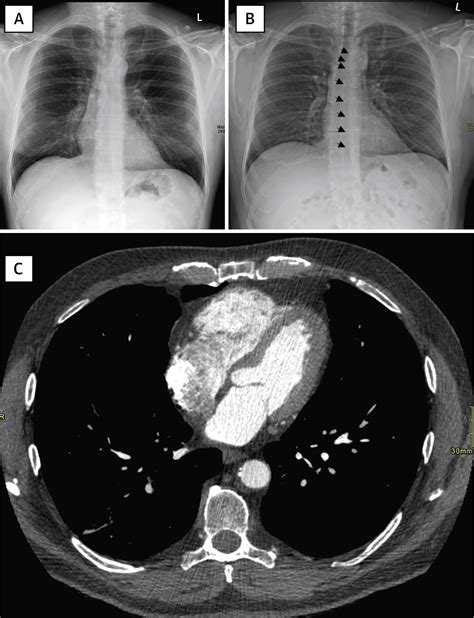

Diagnosing a boot shaped heart involves a combination of imaging techniques and clinical evaluations. Common diagnostic tools include:

• Echocardiogram: An ultrasound of the heart that provides detailed images of the heart's structure and function.

• Electrocardiogram (ECG): A test that records the heart's electrical activity.

• Cardiac Catheterization: A procedure where a thin tube is inserted into the heart to measure pressure and blood flow.

• Magnetic Resonance Imaging (MRI): A detailed imaging technique that provides high-resolution images of the heart.